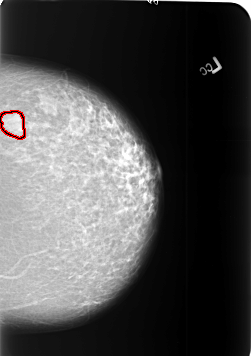

FILE: B_3405_1.LEFT_CC.OVERLAY

TOTAL_ABNORMALITIES 1

ABNORMALITY 1

LESION_TYPE MASS SHAPE LOBULATED MARGINS CIRCUMSCRIBED

ASSESSMENT 4

SUBTLETY 5

PATHOLOGY BENIGN

TOTAL_OUTLINES 1

BOUNDARY